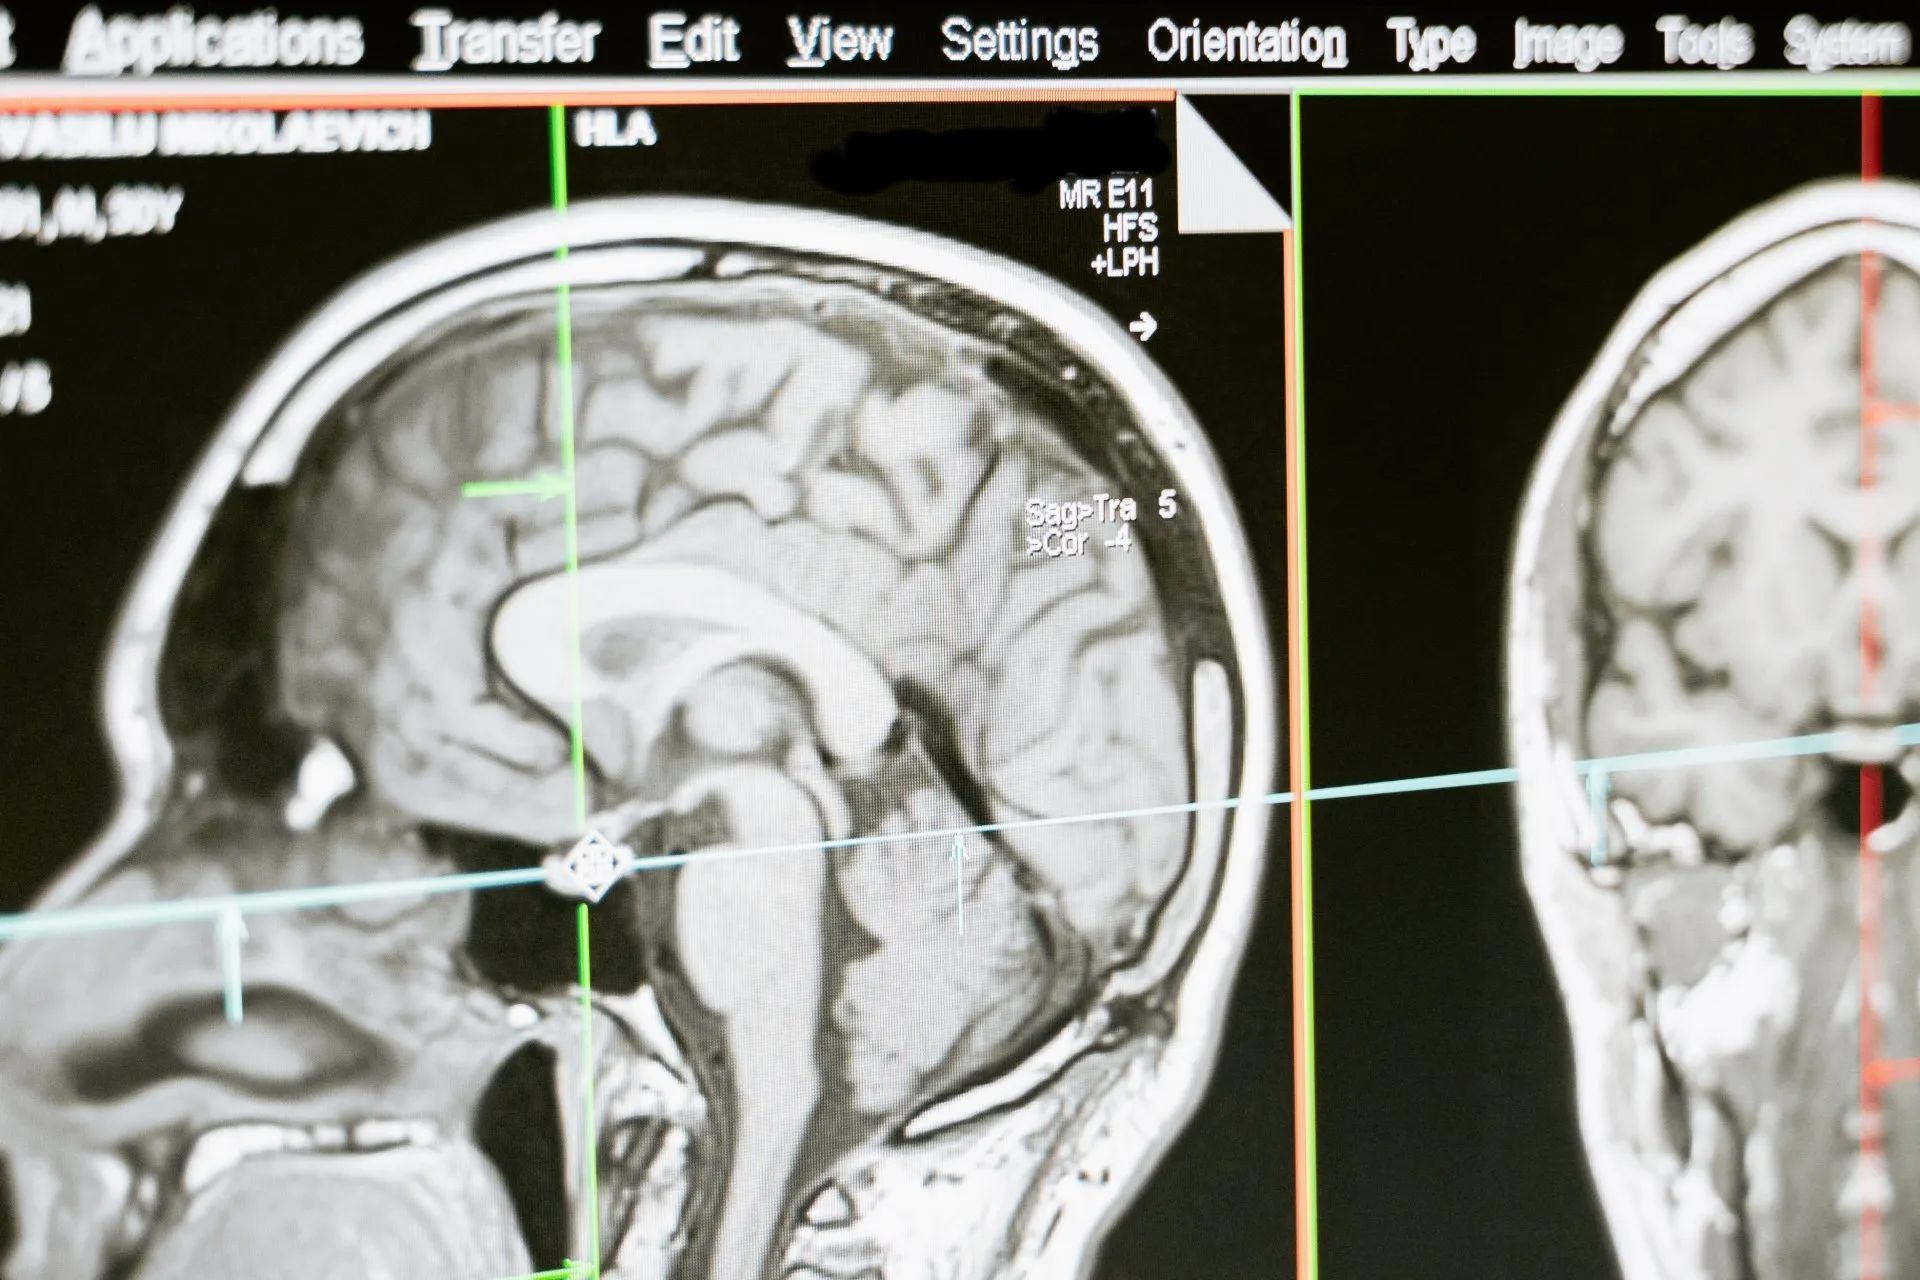

Magnetic resonance imaging is a technique that uses a magnetic field and radio waves to create detailed images of the organs and tissues within your body. Most MRI machines are large, tube-shaped magnets. When you lie inside the machine, the magnetic field temporarily realigns hydrogen atoms in your body. Radio waves cause these aligned atoms to produce very faint signals, which are used to create cross-sectional images — like slices in a loaf of bread. The machine can also be used to produce 3-D images that may be viewed from many different angles. MRI is a noninvasive way for your doctor to examine your organs, tissues and skeletal system. It produces high-resolution images of the inside of the body that help diagnose a variety of problems.